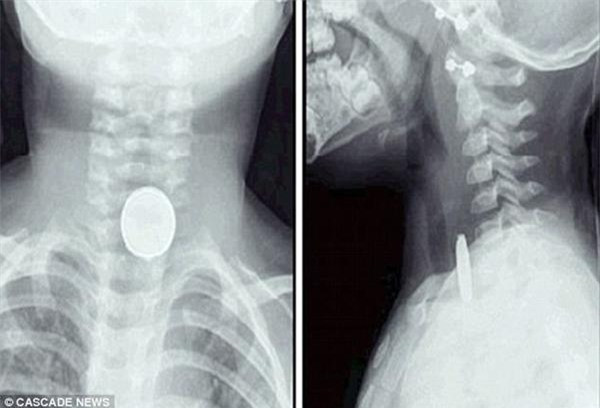

Theo đó, bé gái Molly - con chị Jane đã tự tay tháo cục pin nhỏ xíu trong chiếc điều khiển xe đồ chơi của anh trai và nuốt nó vào miệng. Cô bé được phát hiện kịp thời và lập tức chuyển tới bệnh viện.

Sau cuộc phẫu thuật căng thẳng, Molly đã sống sót. Các bác sĩ cho biết cục pin bị tắc ở thực quản của Molly và nó có thể khiến cô bé mất mạng nếu kéo dài trong vòng 1 giờ đồng hồ. Tuy cuộc phẫu thuật thành công nhưng cục pin ảnh hưởng không nhỏ đến dạ dày của Molly nên cô bé phải dùng thuốc trong vòng 6 tuần để sức khỏe hoàn toàn bình phục.

Bé 2 tuổi suýt tử vong vì nuốt phải cục pin phổ biến trong đồ chơi ảnh 2Nó gây nghẹt đường thở khi trẻ vô tình nuốt phải.